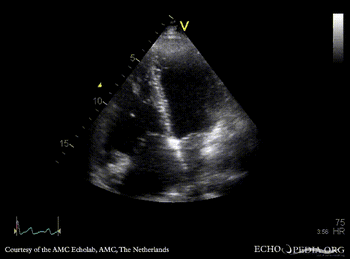

Case 47

| A4CH: ASD type II | A4CH: enlargement of right ventricle and right atrium |